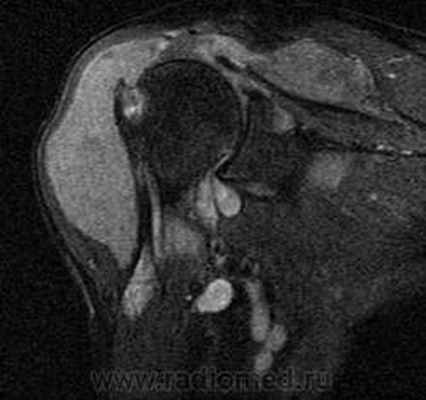

Пигментный виллёзонодулярный синовит - редкое заболевание с доброкачественным течением, характеризующееся пролиферативными изменениями синовиальной оболочки, отложением гемосидерина, образованием ворсинок, паннуса. Две разновидности: виллёзонодулярный бурсит и виллёзонодулярный тендосиновит. Частота - 2 на I 000 000. Преобладающий возраст • Виллёзонодулярный бурсит - 30-40 лет • Виллёзонодулярный тендосиновит -50-60 лет. Преобладающий пол - женский. Этиология. В 30% случаев развитию синовита предшествует травма сустава. Патоморфология. Пролиферация клеток синовиальных оболочек с образованием узлов, содержащих клеточный инфильтрат из фибробластов, лимфоцитов, макрофагов с жировыми включениями. Клиническая картина • Виллёзонодулярный бурсит -моноартрит. Чаще всего (80% случаев) поражается коленный сустав, реже - (с убывающей частотой) тазобедренный, голеностопный и плечевой суставы • Виллёзонодулярный тендосиновит - образование узелков в мышечных сухожилиях и связках сустава. Лабораторные исследования • Увеличение СОЭ • Синовиальная жидкость ксантохромная, с примесью крови • Биопсия синовиальной оболочки: узловая пролиферация, гемосидероз, инфильтрация мононуклеарными клетками. Рентгенологическое исследование • Остеопороз и наличие остеофитов нехарактерны • Артропневмография: множественные округлые дефекты наполнения синовиальной полости, обусловленные наличием узлов или гипертрофированных ворсинок синовиальной оболочки • МРТ - выявление гемосидерина и жировых включений. Артроскопия • Суставной хрящ приобретает коричневую окраску вследствие гемосидероза • Различной величины узлы коричневого цвета. Дифференциальный диагноз • Виллёзонодулярный бурсит • Липома - в аспиратах отсутствует ксантохромная жидкость • Остеоартроз - кисты возникают только на суставных поверхностях, подвергающихся нагрузке, тогда как при пигментном виллёзонодулярном синовите они образуются на всех суставных поверхностях. Остеофи-ты, напротив, более типичны для остеоартроза • Воспалительные арт-ропатии, дебютирующие моноартритом, - ревматоидный артрит, туберкулёзный артрит, анкилозирующий спондилоартрит и др. • Виллёзонодулярный тендосиновит - панглии (околосухожильные кисты): аспираты ганглиев содержат гелеподобную жидкость. Лечение хирургическое • Виллёзонодулярный бурсит • Тотальное иссечение синовиальной оболочки, вероятность рецидива заболевания составляет 25-40% • Лучевая терапия • Виллёзонодулярный тендосиновит - иссечение кист. Синоним. Синовит геморрагический МКБ. М12.2 Ворсинчато-узелковый (виллонодулярный) синовит (пигментный)

- лучевой диагностике (RÖ, МРТ);

Рентген и Артроскопическая картина СХС коленного сустава, при урогенной этиологии (рис. 2-3).![]()

Рис. 5. А. Артроскопическая картина коленного сустава, при пигментно-ворсинчатом узелковом синовите (ПВУС). Б. После артротомии сустава.

В. Состояние хрящевого покрова. Хрящевой покров бедра и надколенника пропитан гемосидерином.